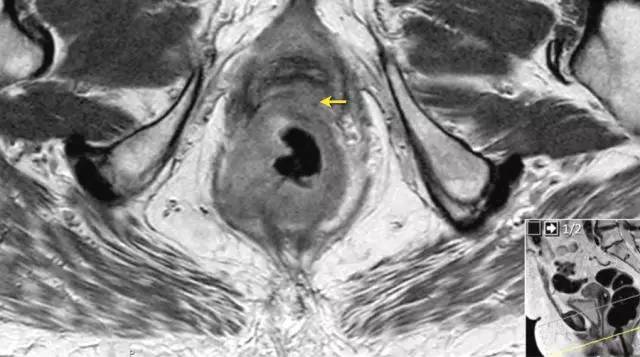

图 16 在矢状 T2W 图像上,直肠和阴道后壁之间有脂肪平面的损失。在轴向图像上,看到肿瘤的相对低的信号强度延伸到阴道的后壁(箭头)

以下 5 幅图例请连续观看:

图 17~21 肿瘤的低信号强度延伸到阴道的后壁(箭头)